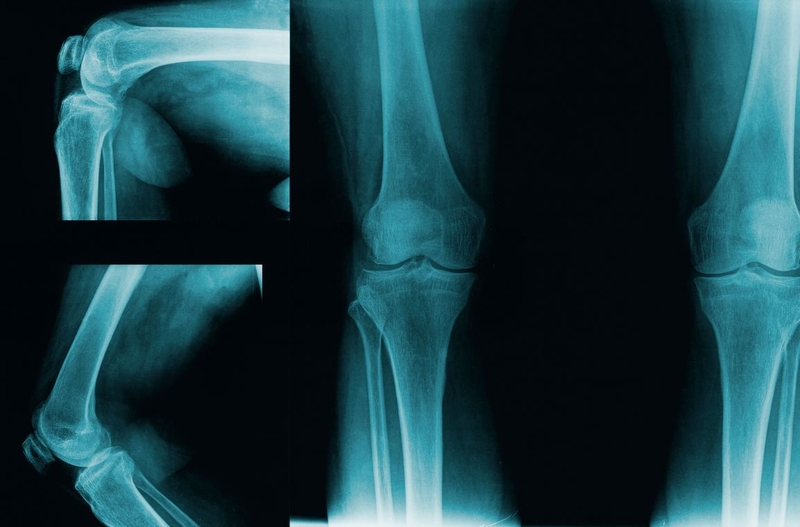

Chụp X quang là một phương pháp chẩn đoán hình ảnh khá thông dụng không chỉ ở Việt Nam mà trên toàn thế giới. Phương pháp này cần sử dụng một thiết bị là máy chụp X quang. Các tia X - một dạng bức xạ điện từ - sẽ đi xuyên qua các cấu trúc từ xương đến cơ hoặc khoang chứa khí trong cơ thể… với cường độ vừa đủ và giúp ghi lại hình ảnh của các cơ quan bên trong cơ thể lên phim chụp X quang. Chụp X quang khớp quy được chỉ định để khảo sát, đánh giá, chẩn đoán các bệnh lý liên quan đến xương, khớp.

Chụp X quang khớp thường quy là một dạng khảo sát khớp chuyên sâu có sử dụng chất cản quang. Chất cản quang hay thuốc cản quang được sử dụng nhằm mục đích tăng hấp thụ tia X. Chất cản quang sẽ được đưa trực tiếp vào các khớp dưới sự theo dõi và chụp ảnh của máy chụp X quang có màn huỳnh quang tăng sáng. Bác sĩ có thể nhìn thấy chuyển động của các cơ quan bên trong khi chất cản quang được tiêm vào trong khớp và phủ đều lên các cấu trúc khớp. Trên màn hình ảnh chụp X quang, chất cản quang giúp cấu trúc khớp hiện lên sáng trắng giúp bác sĩ quan sát được cấu trúc giải phẫu và hoạt động của khớp được khảo sát.